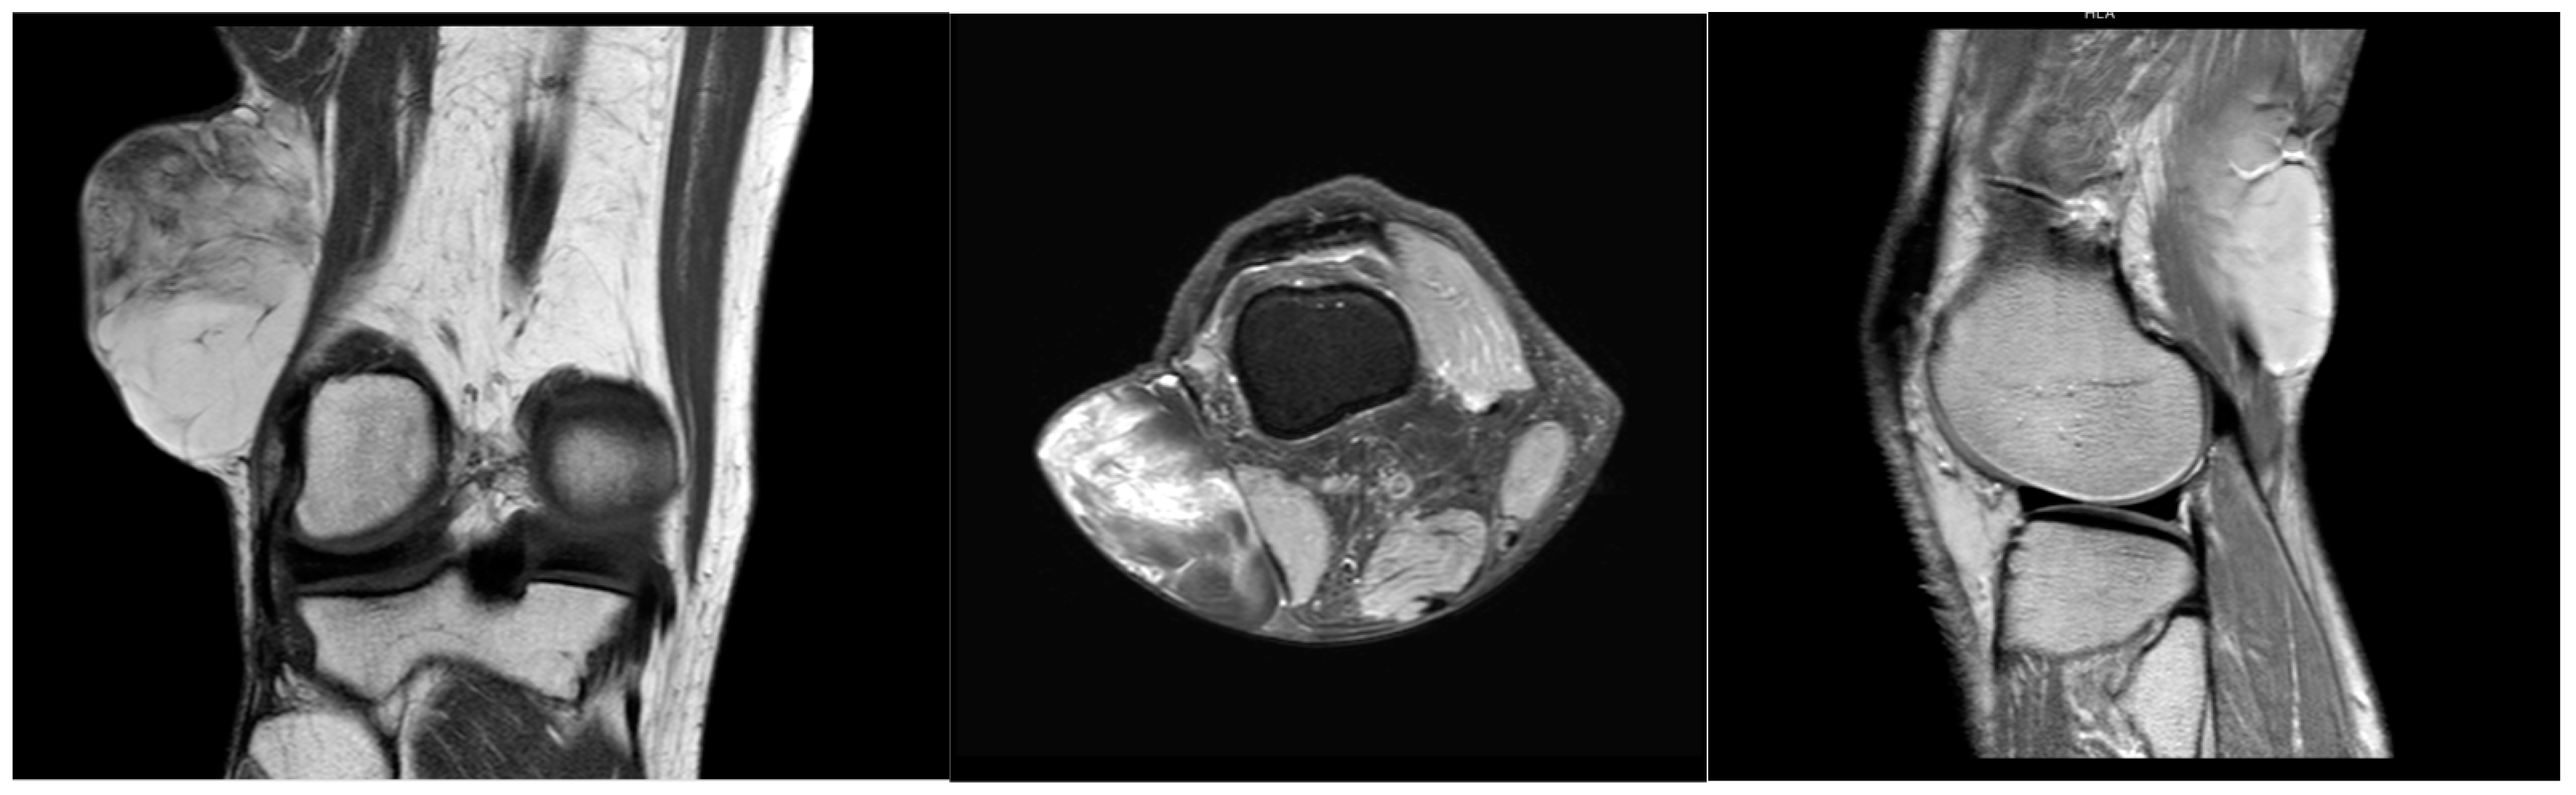

| MRI | T1: homogeneous, low-intensity signal T2: Heterogeneous, high-intensity signal | T1: variable signals; T2: high signals. “Fat ring” on contrast-enhanced T2W MRI | Can appear low in fat, similar to the more aggressive myxoid liposarcoma | Multilobulated, heterogeneous mass T1: hypodense myxoid; enhances with contrast. Hyperdense fatty component (low percentage of tumor) T2: hyperdense myxoid component | T1: hypointense vascular elements; hyperintense fatty components T2: hyperintense vascular elements | High-intensity and well-encapsulated on both T1 and T2 imaging |